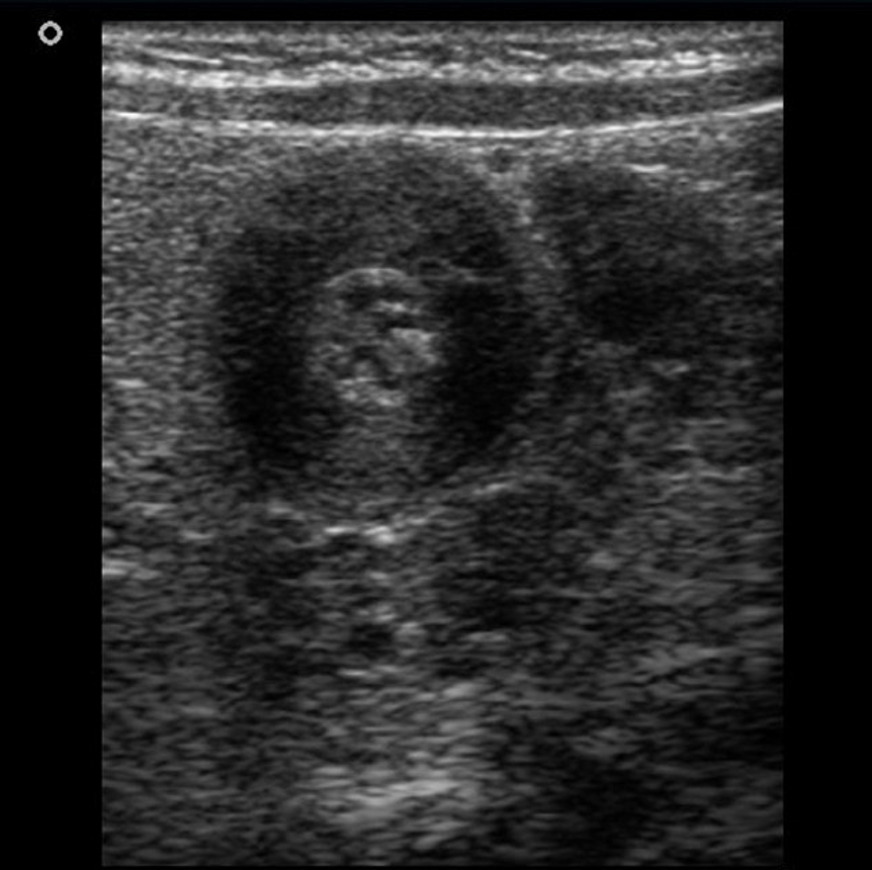

USS abdomen:

Longitudinal view. Case courtesy of Hidayatullah Hamidi, Radiopaedia.org, rID: 51340

Transverse view. Case courtesy of Hidayatullah Hamidi, Radiopaedia.org, rID: 51340

- Pyloric muscle thickness >3 mm and pyloric canal length >15 mm meet the diagnostic criteria for pyloric stenosis in full-term infants. Ultrasound also allows live examination of the flow of gastric contents (or absence of flow) through the pyloric channel, as well as the presence of abnormal peristalsis.

- Transverse views can show the ‘Target sign’ – hypertrophied hypoechoic muscle surrounding echogenic mucosa (see above). Other specific signs include the ‘Cervix sign’ and ‘Antral nipple’ sign.